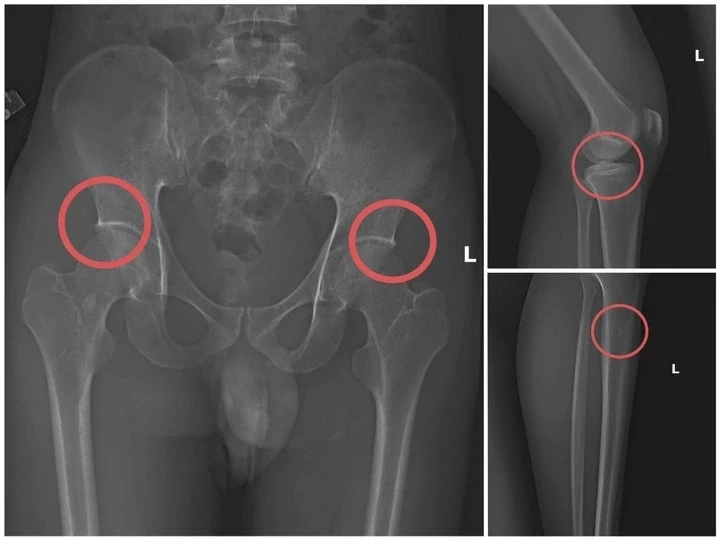

Bản phim chụp XQ một số tổn thương xương do đối tượng tạo ra. Ảnh: Công an tỉnh Phú Thọ